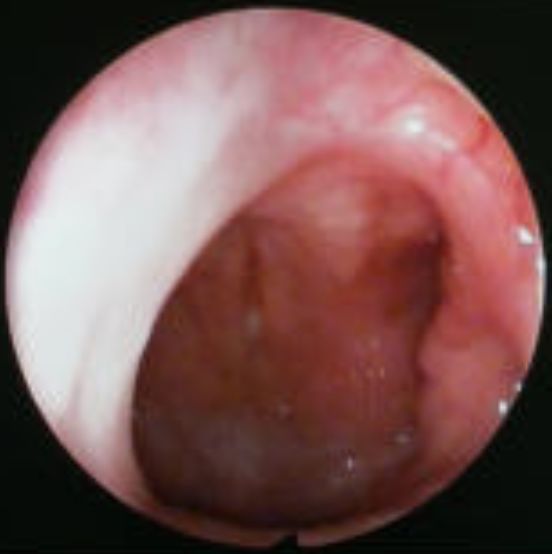

鼻咽镜检查:使用一个带摄像头的内镜经鼻伸入,直接观察腺样体堵塞后鼻孔的程度:

◉25%及以下:I度

◉26%-50%:II度

◉51%-75%:III度

◉76%-100%:IV度

通常III度以上且伴有临床症状的,考虑诊断为腺样体病理性肥大。

▲腺样体IV度肥大